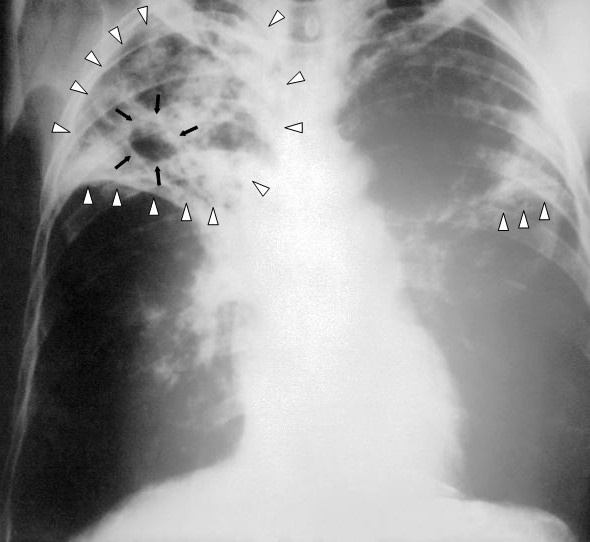

Gruźlica - CDC

Fot. CDC